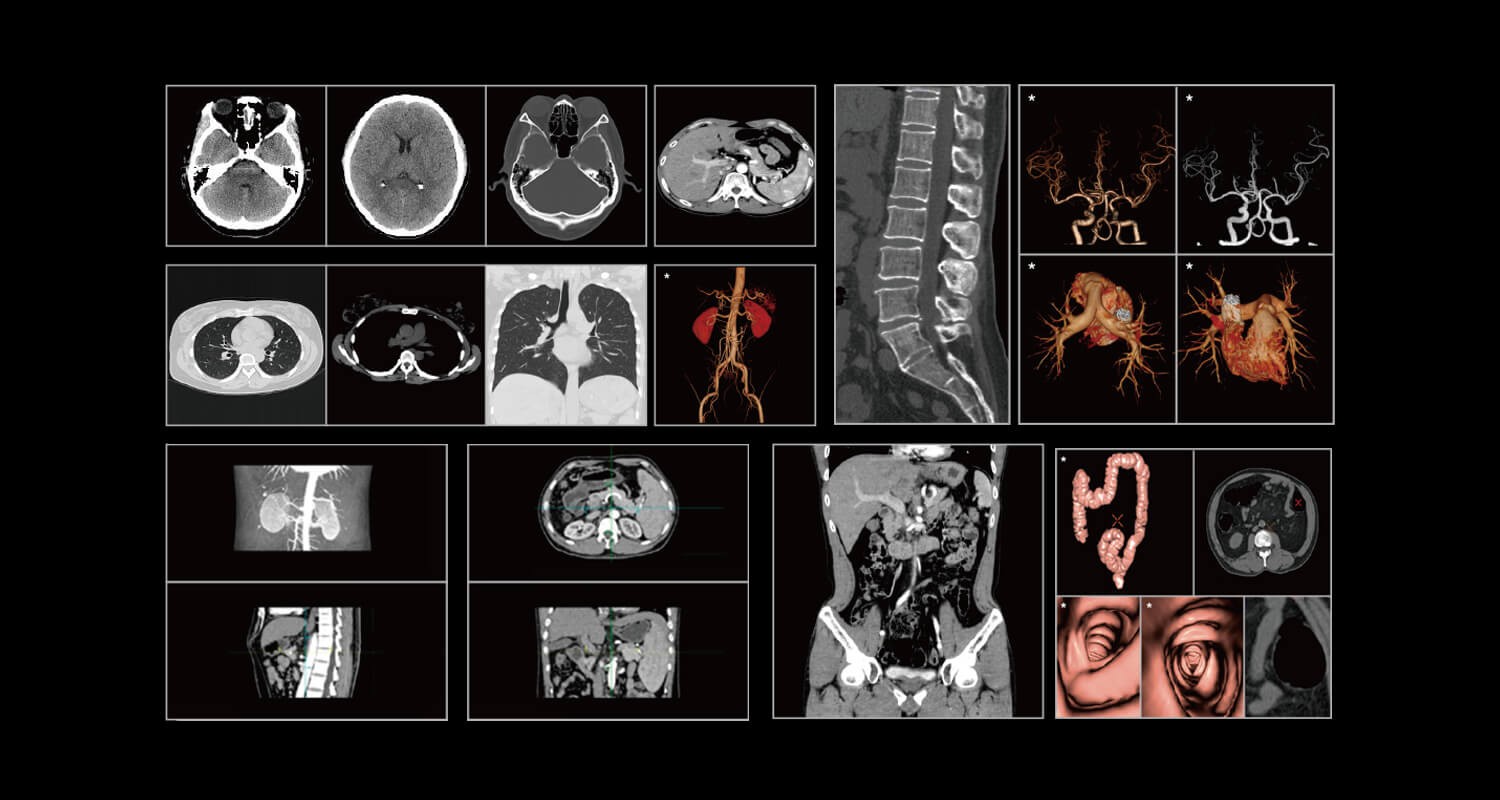

1. Clinical Gallery

車載CT.jpg